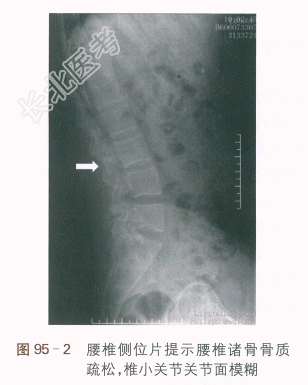

(2)腰椎正侧位X线片:腰椎诸骨骨质疏松,椎小关节及左侧骶髂关节面模糊。如图95-1、图95-2所示。